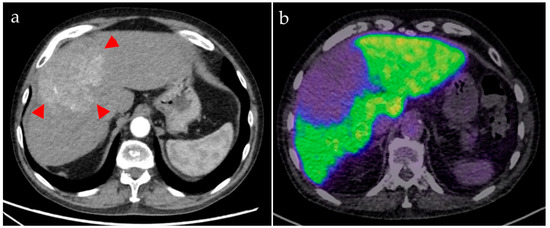

Figure 3. Patient A. The contrast-enhanced CT (a, arterial phase) shows the hypervascularized HCC ((a), arrowheads), involving both liver lobes. [68Ga]Ga-BP-IDA PET/CT (b), acquired 10 min after tracer injection, shows low uptake in the tumor (SUVmax 4.9) compared with healthy liver tissue (SUVmax 18.2).

Two patients (both male; aged 72 and 82 years) underwent [68Ga]Ga-BP-IDA-PET/CT examinations. Activities of 144 MBq and 166 MBq [68Ga]Ga-BP-IDA, respectively, were prepared and injected intravenously. No immediate or delayed complications occurred. After intravenous administration, [68Ga]Ga-BP-IDA showed rapid liver tissue accumulation with a maximum of 41.5% of the injected activity (SUVmax 18.2) (Figure 2, Figure 3 and Figure 4). Biliary excretion was evident after 15 min with passage to the common hepatic duct. Tracer accumulation in the gall bladder was initially seen after 18 min, but continued to increase further, up to a SUVmax of 48.3 after 60 min. After 30 min, the transition to the duodenum and jejunum had already begun (Figure 4). Liver tissue uptake started to decrease slowly after 18 min, but still represented 37.4% of the administered activity after 60 min. No relevant uptake was seen in the spleen or the skeletal system. The radiotracer showed no significant urinary excretion (maximum kidney uptake of 1.7% of the administered activity after 18 min) (Figure 5). [68Ga]Ga-BP-IDA uptake in the HCC was considerably lower than in non-cancerous tissue of the liver but higher than the background activity (Table 2, Figure 3).

Patient A demonstrated a newly diagnosed, well-differentiated HCC in the liver segments IVa/b, V, and VIII without vascular invasion. No extrahepatic metastases were detected. [68Ga]Ga-BP-IDA PET/CT was carried out for pre-interventional evaluation of the liver function distribution, given the large bilobar tumor and the possible damage to healthy liver tissue owing to the planned TARE treatment. It showed a high tumor-to-background ratio with high tracer uptake in the healthy, non-cirrhotic liver tissue (Figure 3). Tracer appeared in the bile ducts between 10 and 18 min after injection (Figure 4 and Figure 5). HCCs can retain a certain degree of metabolic and even excretory liver function, which can be relevant in patients with large tumors and with underlying diffuse liver damage (including, but not limited to, alcohol-related cirrhosis, non-alcoholic fatty liver disease, and hemochromatosis). However, in this case, based on the PET/CT, it was considered that the loss of remaining liver function in the tumor would not be prognostically relevant for the patient.